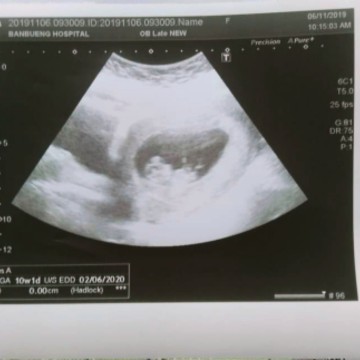

ตอน10วีคค่ะ